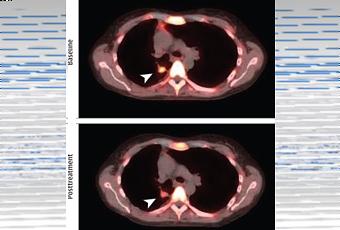

· De plus, la combinaison de palbociclib avec d’autres anti-cancéreux montre aussi de premiers résultats positifs dans le traitement du myélome et certaines tumeurs solides, comme le cancer colorectal (Visuel ci-contre).